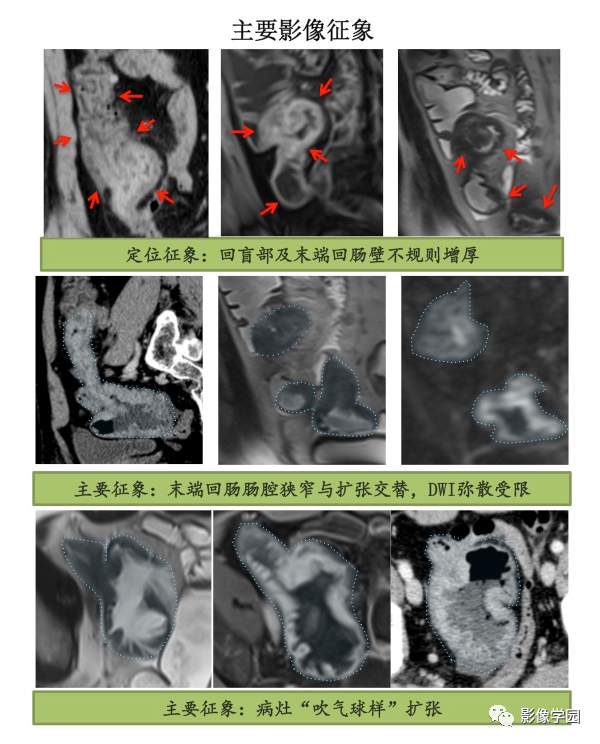

1. 位置:回盲部及末端回肠;

2. 形态:回盲部增厚,肠壁不规则非对称性增厚,最厚处约1.1cm,肠腔狭窄与扩张交替,病灶长度约35cm;

3. CT 平扫:密度不均匀;动态增强:不均匀分层样强化;

4. MR 平扫:T1WI 不均匀低信号,T2WI 不均匀高信号,DWI:黏膜及黏膜下层不均匀高信号;ADC:低信号;动态增强:明显不均匀分层样强化;

5. 其他征象:肠系膜多发稍增大淋巴结;